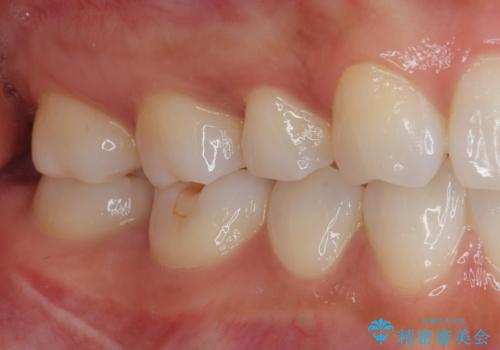

見た目、機能面共に大変喜んでいただきました。

歯と歯の間の虫歯をコンポジットレジンや保険のメタルインレーで治すと段差ができたりして清掃性が悪くなるので、セラミックインレー修復やゴールドインレー修復などの適合の良い詰め物で治療することをオススメします。